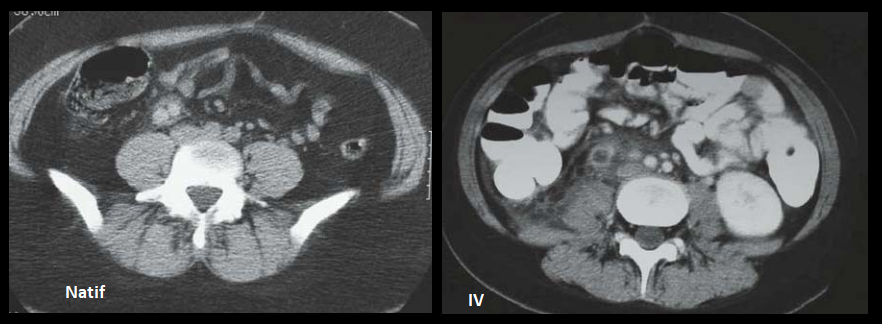

- Thrombophlébite ++

- Douleurs quadrant inférieur (droit++)

- Patientes Post-partum++

- Veine ovariene Droite++